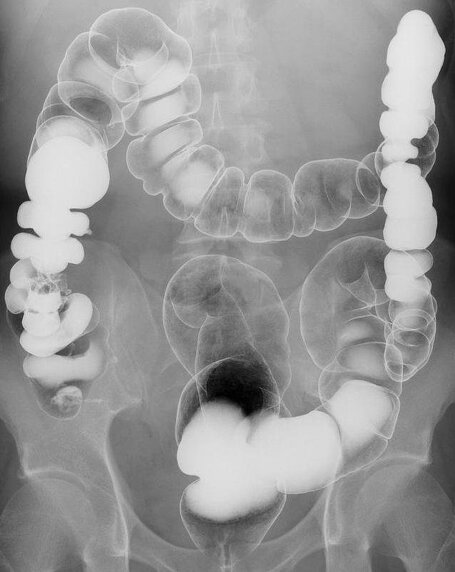

当院ではその他にも、注腸造影検査や瘻孔(ろうこう)造影検査などの検査も可能です。